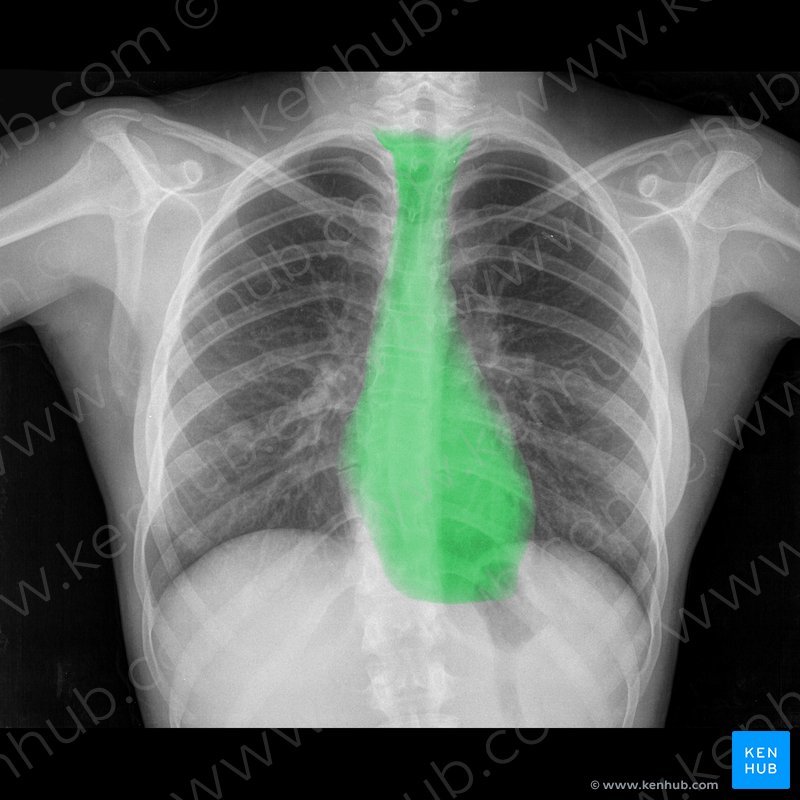

Portion of heart

base

Apex

Position of heart

Mediastinum

The heart is on the ___ side of the mediastinum.

Left